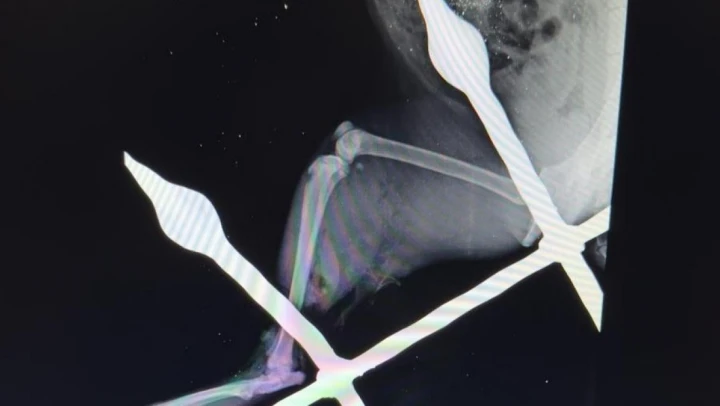

Yaralı kedinin bacağını eski sağlığına kavuşturduklarını anlatan Mersin Büyükşehir Belediyesi Tarımsal Hizmetler Dairesinde Veteriner Hekim olarak görev yapan Yusuf İncir, 'Yapılan ilk tespitler sonucunda, balkon demirinin bacağından yaklaşık 10-15 santimetre civarında geçtiği görülmüştür. Yapılan dezenfeksiyon ve temizlik işlemlerinin ardından, balkon demiri anestezi altındaki kedinin bacağından çıkarıldı. Çıkarılırken dokuya mümkün olduğu kadar zarar vermemeye dikkat ettik. Yaptığımız tespitlerde kaslardan bir tanesinin kopmuş olduğu, yalnız sinir dokusunda herhangi bir hasar oluşmadığı tespit edilmiştir. Yapılan yara temizliği ve dezenfeksiyonun ardından, kopan kas kısmı dikişle tekrar eski haline getirildi. Dezenfeksiyonun ardından, yırtılan ve hasar gören dokuların dikiş işlemini gerçekleştirdikten sonra, deri dikişi ile işlemimizi tamamladık. 12 gün zarfında kedimiz sağlığına kavuştu' ifadelerine yer verdi.